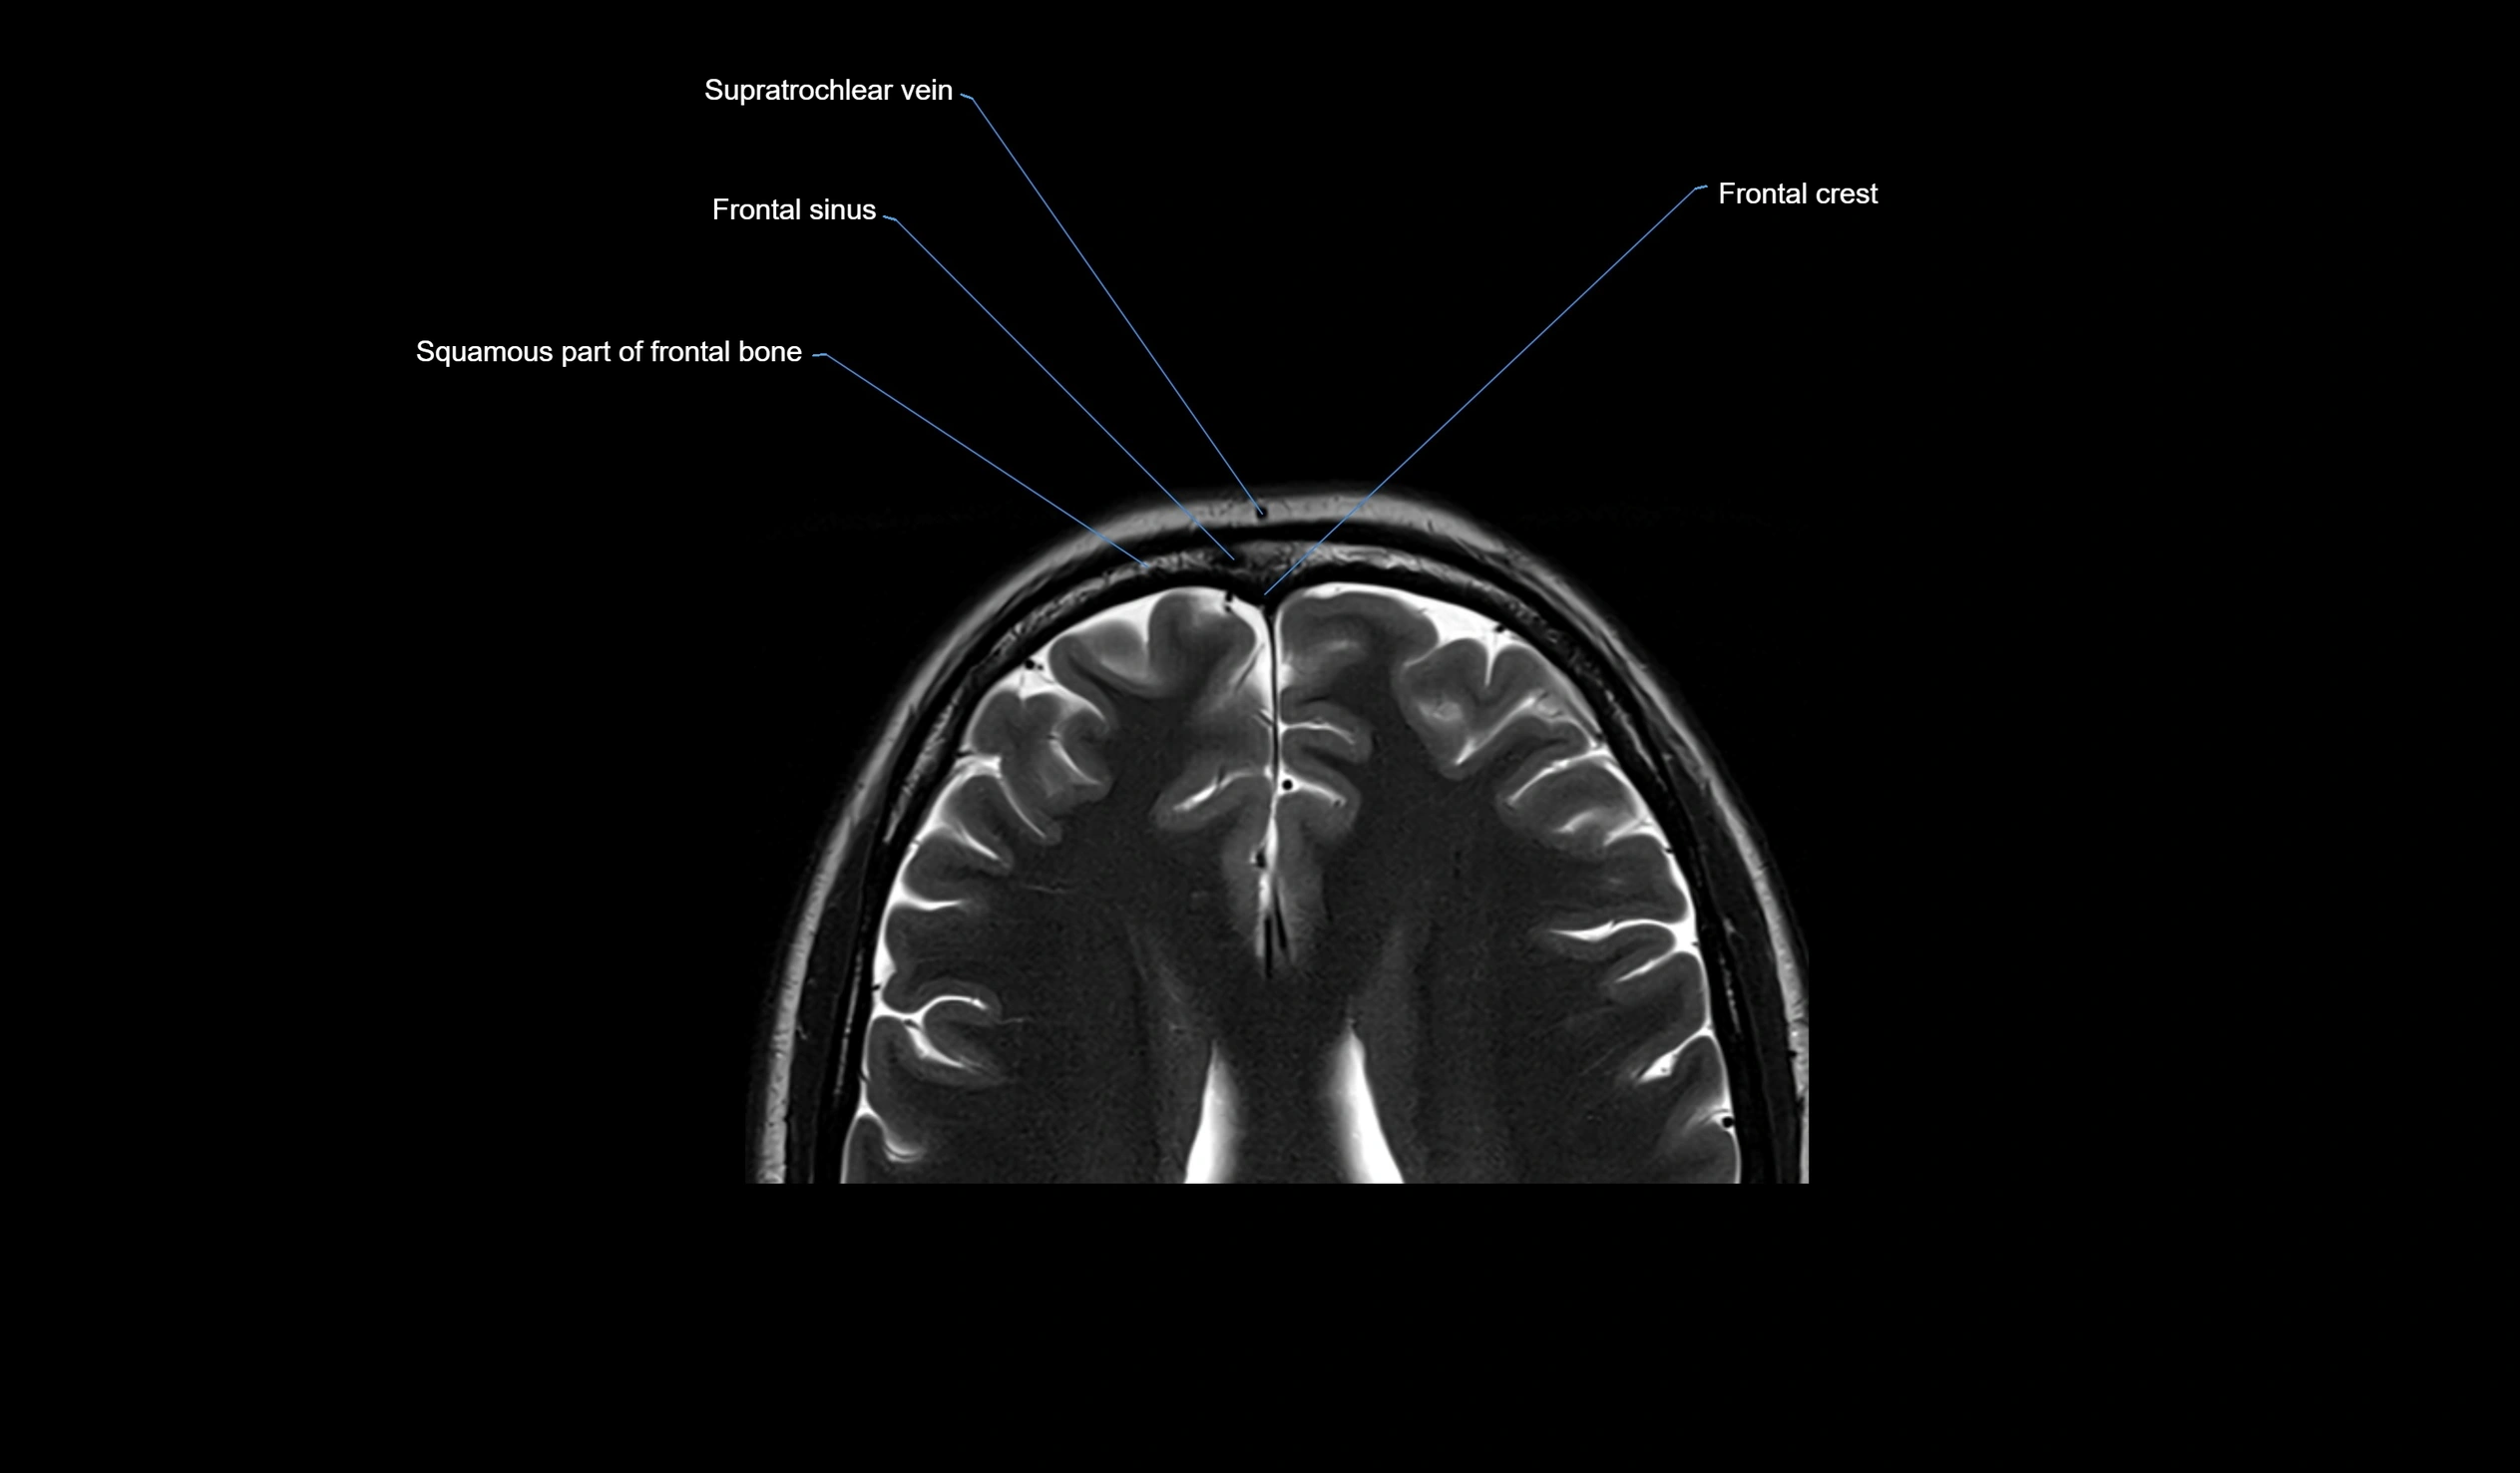

MRI images